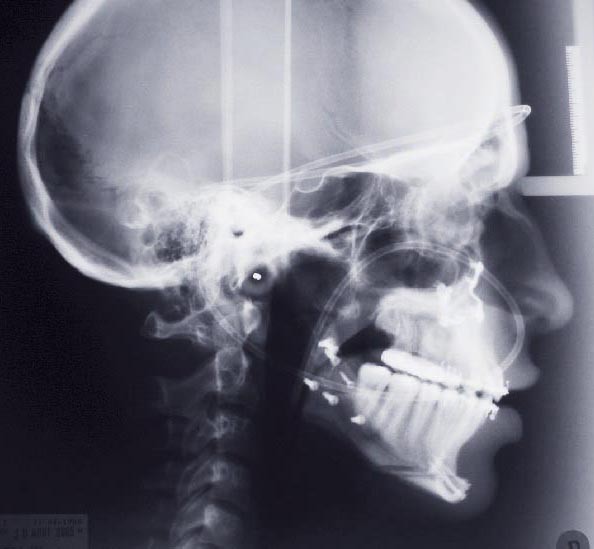

Les mouvements de décompensations sagittales et transversales sont réalisés à l’aide des tractions inter-arcades. La réévaluation céphalométrique et l’analyse des moulages confirment l’indication d’une chirurgie maxillaire de propulsion et d’une chirurgie mandibulaire par clivage bilatéral des branches montantes pour un recul mandibulaire modéré accompagné d’une génioplastie bidimensionnelle élargie qui rappelle la technique de Chin Wing.